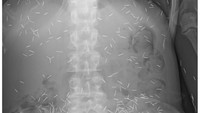

Penampakan X-ray seorang wanita di Malaysia yang mengeluh sakit perut nyeri perut kronis. Setelah diperiksa, ternyata ada banyak jarum di tubuhnya. (Foto: Journal of Radiology Case Reports)

Diprediksi ada sekitar 800 jarum 'susuk' yang bersarang di tubuh wanita ini. Radiografi perut dari pasien yang sama menunjukkan jarum berada paling banyak di area panggul. (Foto: Journal of Radiology Case Reports)